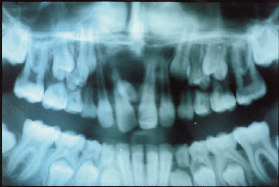

Thiếu răng:

Răng thiếu thường gặp nhất là thiếu Răng khôn; kế tiếp là răng cối nhỏ II hàm dưới; răng cửa bên hàm trên. Răng cối nhỏ I hàm trên; răng cửa giữa hàm dưới … Các răng thiếu này không phát triển hoặc bị ngầm, sẽ gây hiện tượng dư chỗ và các răng mọc lên sẽ nghiêng hoặc di chuyển về chỗ thiếu răng này.